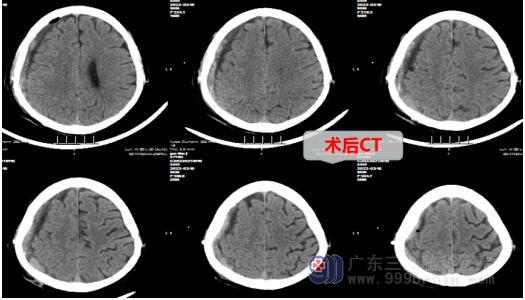

术后,郭爷爷恢复清醒,四肢肌力V级,复查CT显示脑室及中线结构轻度左偏已缓解。